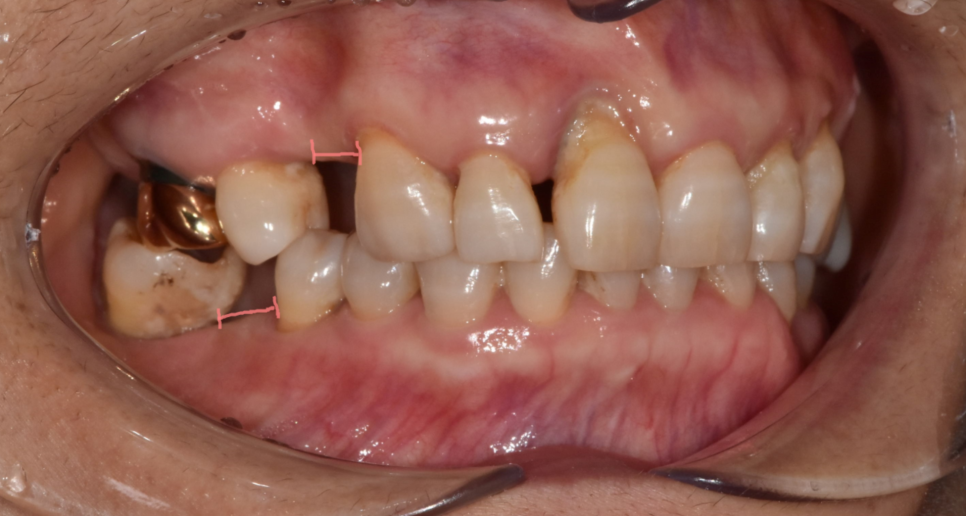

두번째, 치아 움직임으로 공간이 부족

치아가 빠진 상태로 장기간 방치하게되면

주변 치아가 이동하게 되고

맞물리는 치아는 올라오거나 내려오게 되는 등

치아의 위치 변화가 발생합니다.

240423 치아가 빠지고 주변으로 움직인 경우

이러한 상황에서는 브릿지 치료가 대안으로 고려되기도 합니다.

임플란트를 심게 되더라도

공간이 좁아 보철물 크기도 작게 제작될 수 있고

음식물이 낀다는 단점이 있거든요.